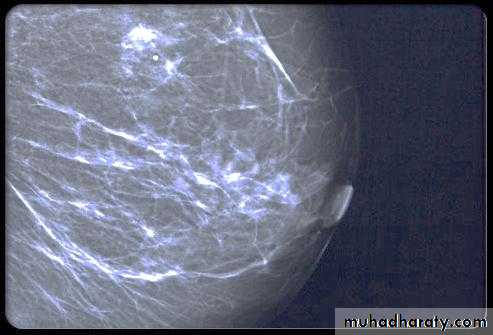

Breast density & who can U detect a mass lesion

Your mammogram report must take in consideration & assessment the breast density. Breast density is based on how fibrous and glandular tissue tissues are distributed in your breast, vs. how much of your breast is made up fatty tissue.

Dense breasts are not abnormal, but they are linked to a higher risk of breast cancer. We know that dense breast tissue can make it harder to find cancers on a mammogram. Still experts do not agree what other tests, if any, should be done in addition to mammograms in women with dense breasts who aren’t in a high-risk group (based on gene mutations, breast cancer in the family, or other factors